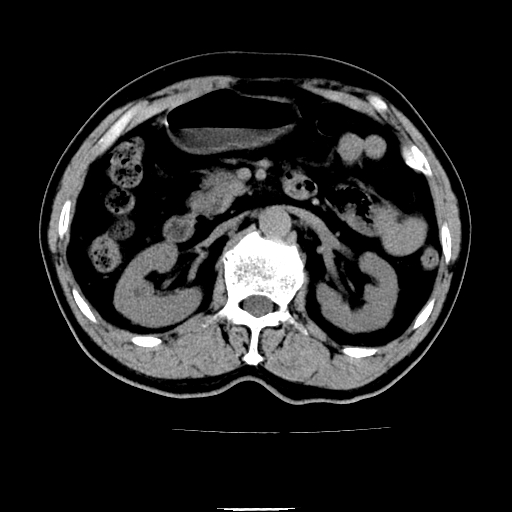

以下是引用chenqiong在2010-3-25 20:56:00的发言:[br]1、胆囊炎,胆囊息肉[br]2、肝内胆管及胆总管扩张,胆总管下端结石[br]3、十二指肠乳头旁憩室

以下是引用zxl51642在2010-3-26 10:47:00的发言:[br]胆囊炎,胆囊息肉,胆总管扩张,但未看到明显肿块,肝内胆管扩张不像恶性,炎性狭窄或阴性结石可能吧,建议mrcp,右肾小囊肿